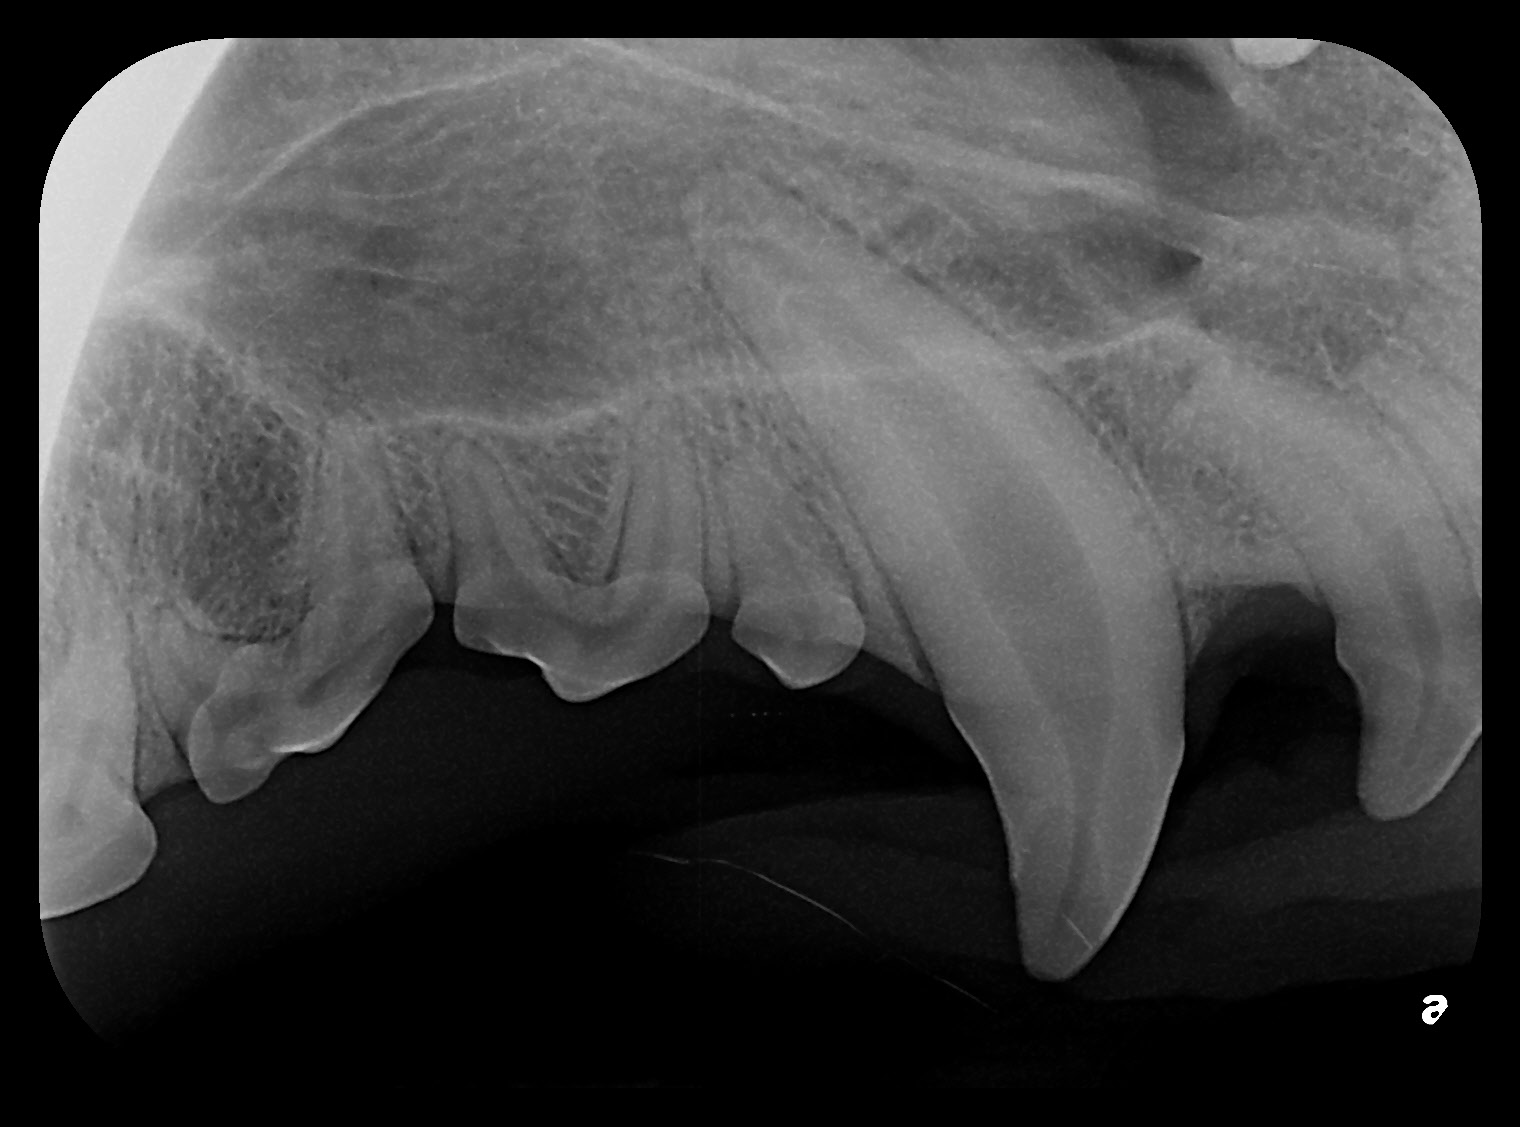

- Root canal therapy (endodontic treatment): We remove infected or dead pulp, thoroughly clean and seal the root canal system, and restore the tooth with a filling or crown. This is often the preferred choice for preserving important teeth and maintaining function.

Our team uses state-of-the-art diagnostics and gentle techniques to ensure your pet’s comfort throughout treatment. Before-and-after photos illustrate the clinical and radiographic results of a successful canine tooth root canal, showing how we can preserve and restore teeth to full function.